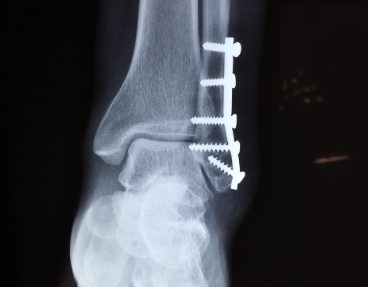

병원에서는 손상 정도를 확인하기 위해 X-ray, 초음파, MRI 검사를 진행합니다. 골절이 동반되지 않았더라도, 인대의 완전 파열 여부를 확인해야 치료 방법이 달라집니다.

- 수술적 치료 (완전 파열)

- 끊어진 인대를 봉합하거나, 필요 시 재건술 시행

- 수술 후 약 6주 이상 고정